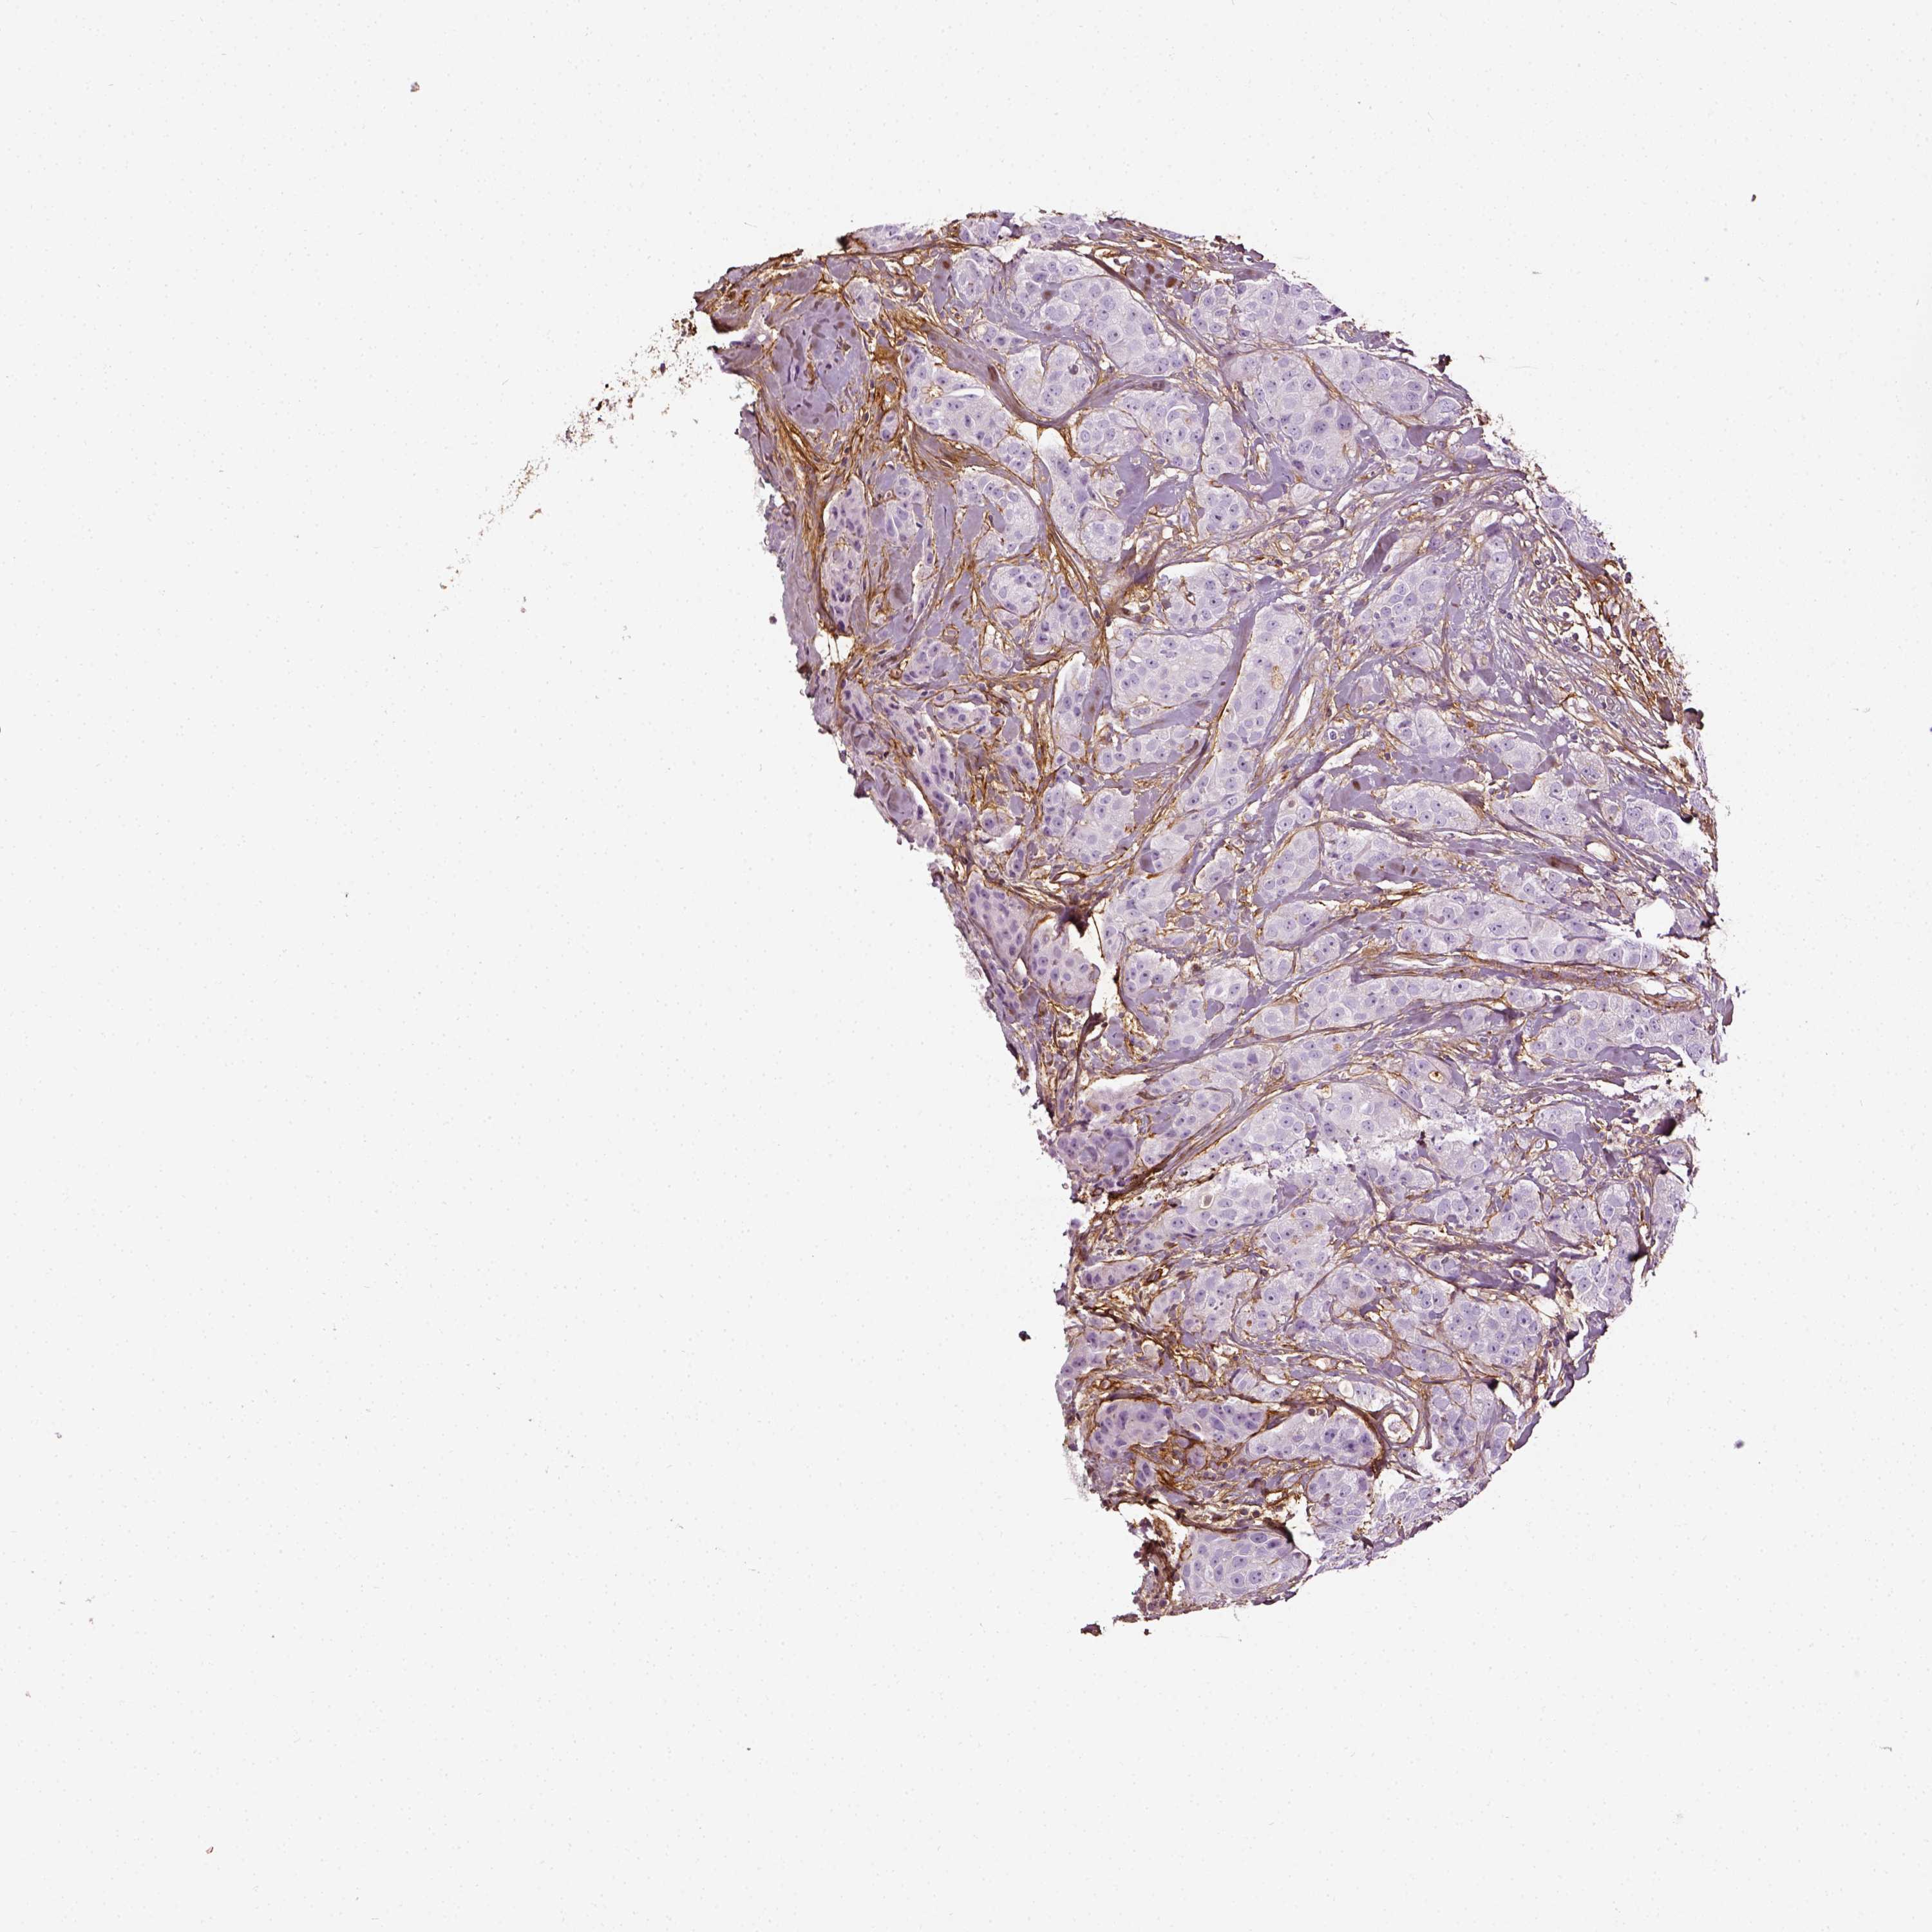

BRCA TCGA BRCA VALIDATION PROTEIN EXPRESSION